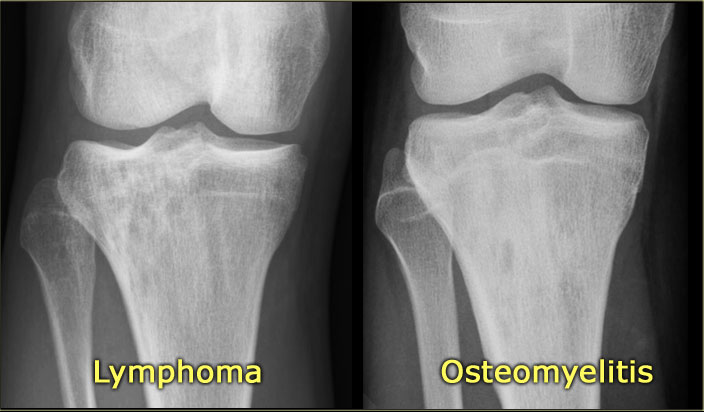

Here a NHL presenting as a non-specific ill-defined mixed osteolytic-sclerotic lesion in the proximal tibia.

Here a bone lesion in a patient with known NHL.

The imaging findings are non specific.

The images show another case of osteomyelitis.

Notice the ill-defined osteolysis with a permeative pattern of destruction of the cortex and an interrupted periosteal reaction.

In a child the differential diagnosis includes a Ewing sarcoma and an eosinophilic granuloma.